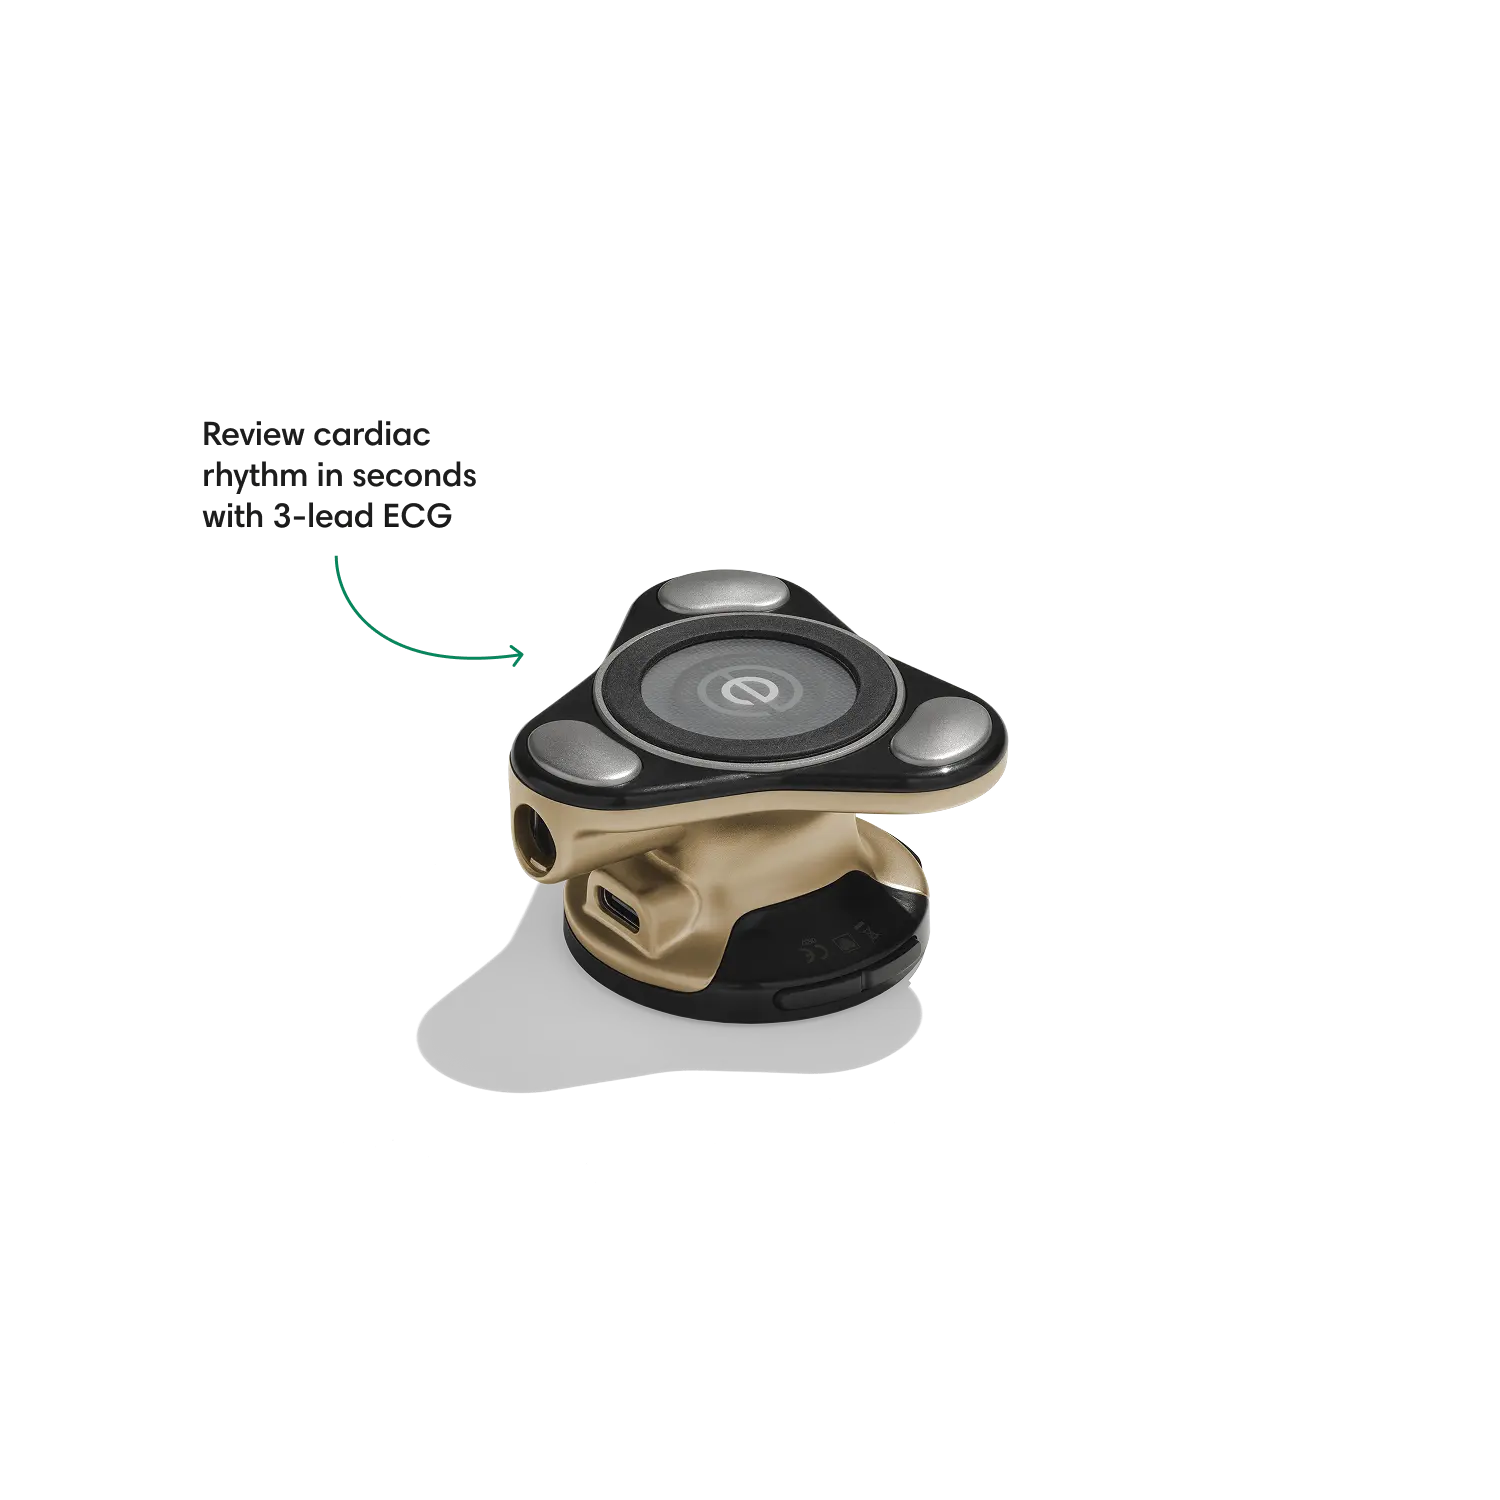

Go beyond sound alone.

For the first time ever, measure heart rate, visualize 3-lead ECG, and see detection results — right on a built-in, full-color display.